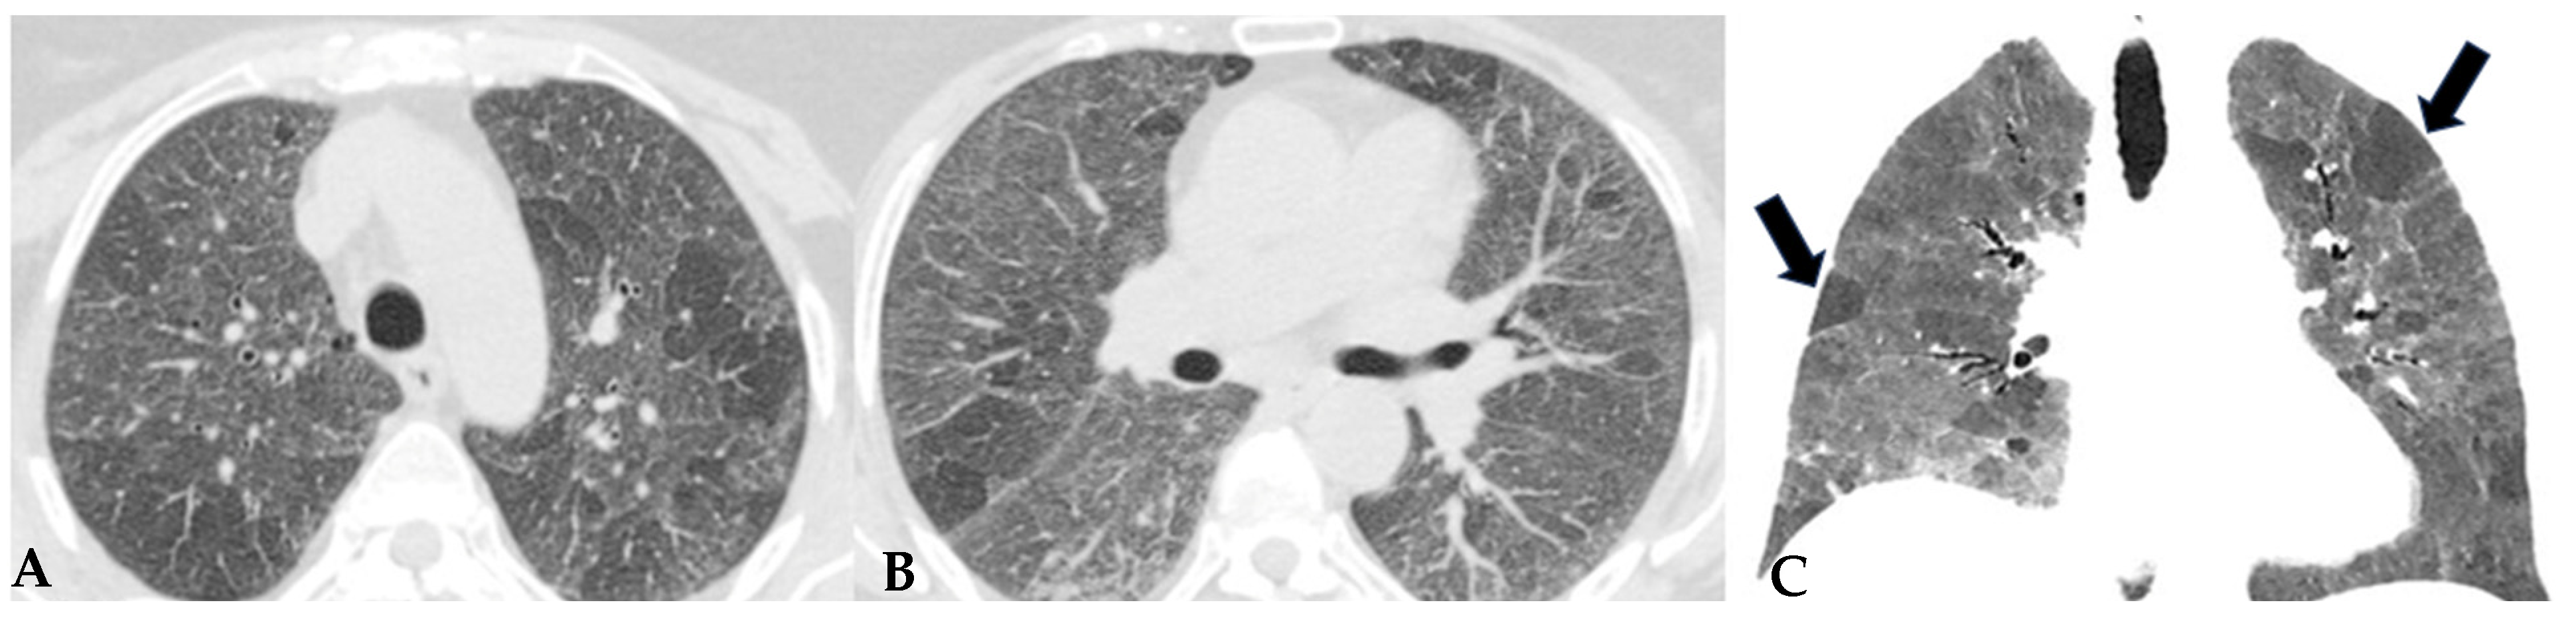

HP, as extensively described, represents a diffuse infiltrative disorder caused by sensitization to inhaled antigens that trigger an exuberant and abnormal immune response in the bronchial and alveolar regions of the lungs. Disease susceptibility is regulated by host-related factors, including genetic variations influencing immune response, as well as antigen properties and exposure-related factors. A cluster of patients with fibrotic ILDs, particularly those with FHP and those with CTD-ILDs, show a susceptibility to developing a progressive fibrosing phenotype despite proper therapeutic management: “Progressive Pulmonary Fibrosis” (PPF-ILD) [24,25]. Literature data estimate that approximately 18–32% of patients diagnosed with non-idiopathic fibrotic ILD (non-IPF) may progress towards a progressive phenotype with unfavorable outcomes [26]. This progressive cluster includes different pathologies that share some markers of fibrogenetic activation, showing remarkable similarities with the clinical course observed in aggressive IPF, a prototype of unfavorable prognosis in fibrotic ILDs. Shared pathogenetic mechanisms cause collagen matrix deposition, distorting interstitial architecture and leading to advanced fibrotic damage. This results in a progressive decline in lung function, exacerbated symptoms like dry cough and dyspnea, nutritional deficits and an overall decrease in quality of life. In some cases, this can lead to treatment refractoriness and early mortality. From a genomic perspective, advancements are being made in the search for in vivo biomarkers (liquid biopsy: evaluation of biological fluids such as saliva, sputum, blood, urine, tissues, etc.) with assessment of genomic, proteomic and metabolomic profiles. This would allow for a much more detailed stratification of patients with ILDs in general and those with progressive fibrotic forms in particular [27,28]. This would enable a multimodal cross-sectional approach to understand markers that can further explain aspects of physical decline capable of influencing patient nutrition, thus accelerating physical decline [29]. For this reason, the new aspects related to the decoding of “omics” markers could impact significantly new therapeutic profiles. From a purely radiological standpoint, the new guidelines on IPF and progressive forms make it evident how the role of HRCT evaluation in patients diagnosed with fibrotic ILD can be indispensable in the “timing of serial assessment”, with accurate longitudinal evaluations and side-by-side visual comparison of HRCTs, integrating clinical and functional data and demonstrating possible progression (Figure 13). No standardized protocols exist for treating HP. Prioritizing antigen avoidance is crucial. Though immunosuppressants are frequently employed, their efficacy in slowing fibrotic disease progression remains unproven. The US Food and Drug Administration has sanctioned Nintedanib, a tyrosine kinase inhibitor, for impeding the advancement of chronic fibrosing ILDs, encompassing the progressive fibrotic form of HP. Non-pharmacological measures like oxygen therapy, pulmonary rehabilitation and supportive care play pivotal roles in the comprehensive management of individuals with progressive HP. The new therapeutic frontiers, therefore, open significantly encouraging scenarios in patients with progressive forms, as even these secondary fibrosing forms, previously orphaned of therapy due to their evolutionary characteristics, can finally benefit from antifibrotic therapy like idiopathic forms.

Progressive FHP pattern. Axial chest HRCT scan. Longitudinal assessment of a rapidly progressive form of HP: evident transitions from a cellular form characterized by GGO/centrilobular fluffy nodules and mosaic attenuation (A) to a fibrotic form (B), characterized by distorted fibrotic GGO, traction bronchiectasis and bronchiolectasis (blue shape), a clear increase in the extensive area of air trapping on the right (yellow circle) and an area of lung spared from the pathological process (red box): a picture of progressive FHP with a “three density pattern”.